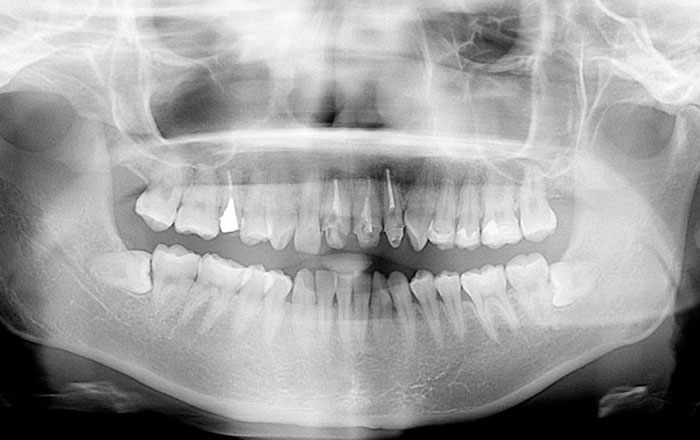

親知らずとは、前歯から奥歯側へ数えて、8番目の歯のことです。

「第三大臼歯」が正式な名前で、智歯(ちし)とも呼ばれています。

親知らずは必ず生えるという訳ではなく、日本人ではおよそ30%の確率で、先天的に親知らずがないと言われています。

親知らずが生えてくる年齢は、10代後半〜20代前半だと言われています。